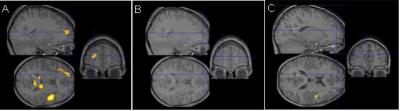

The idea that they may have an underlying problem processing sound was introduced by Paula Tallal, PhD, of Rutgers University in the 1970s, but it has never been tested using brain imaging. Gaab used functional MRI imaging (fMRI) to examine how the brains of 9- to 12-year old children with developmental dyslexia, and normal readers, responded to sounds, both before and after using educational software called Fast ForWord Language, designed in part by Tallal, a co-author on the study.

Gaab first tested how the children's brains responded to two types of sounds: fast-changing and slow-changing. These sounds were not language, but resembled vocal patterns found in speech. As Gaab watched using brain fMRI, the children listened to the sounds through headphones. The fast-changing sounds changed in pitch or other acoustic qualities quickly—over tens of milliseconds—as in normal speech. By contrast, slow-changing sounds changed over only hundreds of milliseconds.

In typical readers, 11 brain areas became more active when the children listened to fast-changing, compared to slow-changing, sounds. Gaab set this as "normal." In dyslexic children, the fast-changing sounds didn't trigger this ramped-up brain activity. Instead, dyslexic children processed the fast-changing sounds as if they were slow-changing—using the same brain areas, at the same lower intensity. "This is obviously wrong," says Gaab.

The repetitive exercises appeared to rewire the dyslexic children's brains: after eight weeks of daily sessions—about 60 hours total—their brains responded more like typical readers' when processing fast-changing sounds, and their reading improved. It's unclear, though, whether the improvement lasts beyond a few weeks, since follow-up tests were not done.